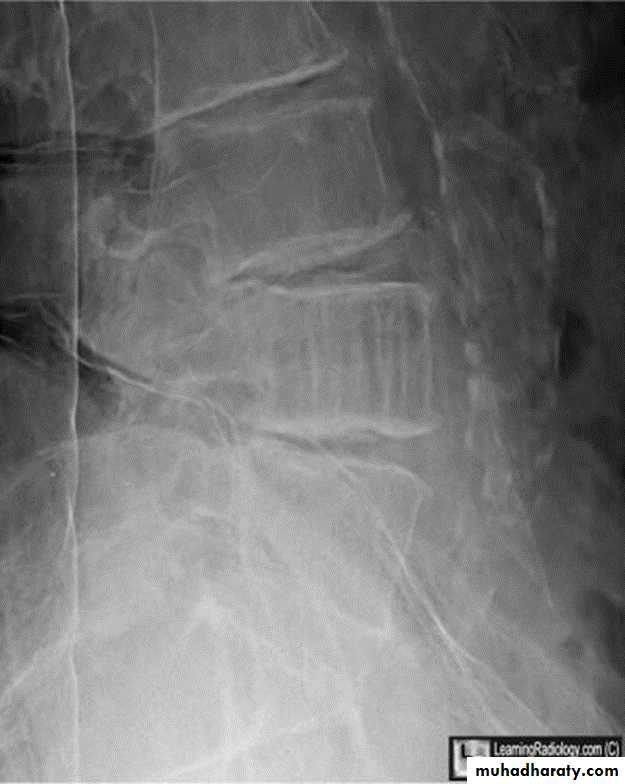

Spondylolysis and spondylolisthesis

Spondylolisthesis: is a term denoting fore ward or backward movement of a vertebra relative to the vertebral segment below, typically due to spondylolysis (pars interarticularis defects) .Spondylolysis: Spondylolysis is a defect in the pars interarticularis of the neural arch, the portion of the neural arch that connects the superior and inferior articular facet in which cause defect in the neck of scotty dog .

scotty dog sign refers to the normal appearance of the lumbar spine when seen on oblique radiographic projection. On oblique views, the posterior elements of vertebra form the figure of a Scotty dog with:

the transverse process being the nose

the pedicle forming the eye

the inferior articular facet being the front leg

the superior articular facet representing the ear

the pars interarticularis (the portion of the lamina that lies between the facets) equivalent to the neck of the dog.